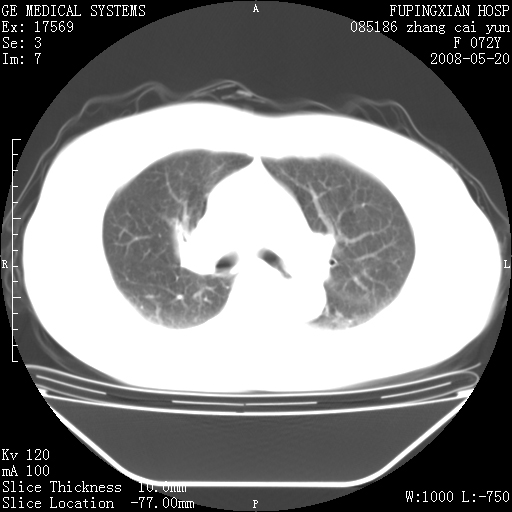

有节段性阻塞性肺炎与不张,近段支气管狭窄,周围散在肿大淋巴结影,以周围型肺癌可能性大,建议纤支镜检查。

右肺上叶实变影,内见支气管充气征,右上叶支气管通畅,肺门区未见软组织密度影,抗炎治疗有效,考虑炎症,建议继续抗炎治疗复查。

考虑为:右肺上叶感染性病变。建议:1)继续抗炎治疗后复查。2)必要时行纤支镜检查。

右上肺实变,间内有支气管充气征,考虑炎症,建议抗炎后复查

右肺上叶感染性病变。建议:1)继续抗炎治疗后复查。2)必要时行纤支镜检查。